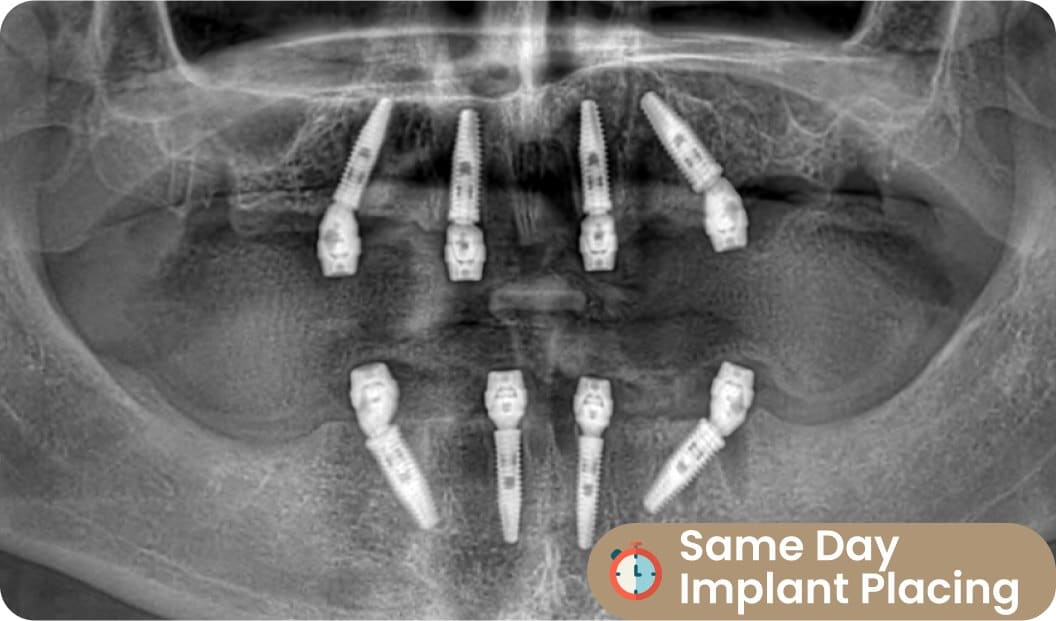

2) Dental Implant Placing

Our surgeons and cosmetic doctors place per implant very easily. Thanks to the digital implantology tech that we are using in Antalya 2022.

Implant Placing: Same Day (Day 1ST)

After using 3D X-Ray, the surgical team examines the gums and roots. Then, he recommends the appropriate implant model and brands to the patient. After the decision is made with the patients, surgical intervention begins. As Dentafly, we use 100% digital systems when performing surgical interventions on patients in our branch in Antalya.

X-Guide All on Four techniques and advanced surgical devices focus on providing a comfortable time for the patient at every stage. With the start of All on Four treatment, the intervention to be made on the teeth and gums is planned by the surgeon.

At this stage, a demo session is held and the patient is told about the intervention and how long it will take. If the patient does not want an additional intervention such as general anesthesia, all on four implant placement will wait on the same day.